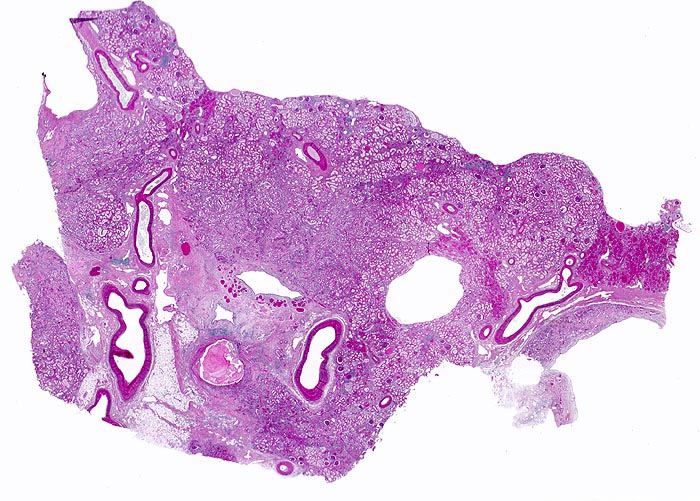

Morphologie: Die Nieren sind mehr oder weniger stark verkleinert. Die Oberfläche ist durch breitbasige und U-förmige narbige Einziehungen über dilatierten oder deformierten Nierenkelchen grob gebuckelt. Die Narben sind verschieden gross und aufgrund der starken Vaskularisation rot gefärbt. (Vaskuläre Narben sind dagegen weiss und scharf begrenzt). Das Endstadium bildet eine fein granulierte Schrumpfniere (=totale pyelonephritische Narbenniere). Die Mark-Rindengrenze ist verwaschen. Die Narben sind auf Schnitt keilförmig und reichen mit der Keilspitze bis ans Nierenbecken. Die Nierenbeckenschleimhaut ist stark verdickt und eventuell gerötet. Papillennekrosen sind besonders bei Diabetikern und Analgetikanephropathie häufig.

Histologisch finden sich neben völlig unverändertem Parenchym herdförmige Infiltrate aus Lymphozyten, Plasmazellen, Histiozyten und bei akutem Schub zusätzlich neutrophile Granulozyten. Das destruierte Gewebe wird durch Granulationsgewebe im Intersititum organisiert. Gruppen erhaltener Tubuli mit vergrössertem Durchmesser und abgeflachtem Epithel gefüllt mit Harnmukoid (=Tamm-Horsfall Protein und/oder IgA) bilden Pseudostrumaherde ( 1793). Diese sind ein wichtiger Hinweis aber kein Beweis für chronische Pyelonephritis. Bei Kindern finden sich oft zusätzlich Lymphfollikel. Glomeruli kollabieren und zeigen eine konzentrische periglomeruläre Fibrose. Oft findet sich eine Arteriolosklerose und eine adaptative Intimafibrose grösserer Arterien. Obligat findet sich eine schwere chronische Pyelitis sowie eine Fibrose von Nierenbecken und Nierenmark. Bei fortgeschrittener bilateraler Nierenschädigung kommt es zum Auftreten einer Überlastungsglomerulopathie, die meist unter dem Bild einer segmentalen fokalen Glomerulosklerose in Erscheinung tritt.